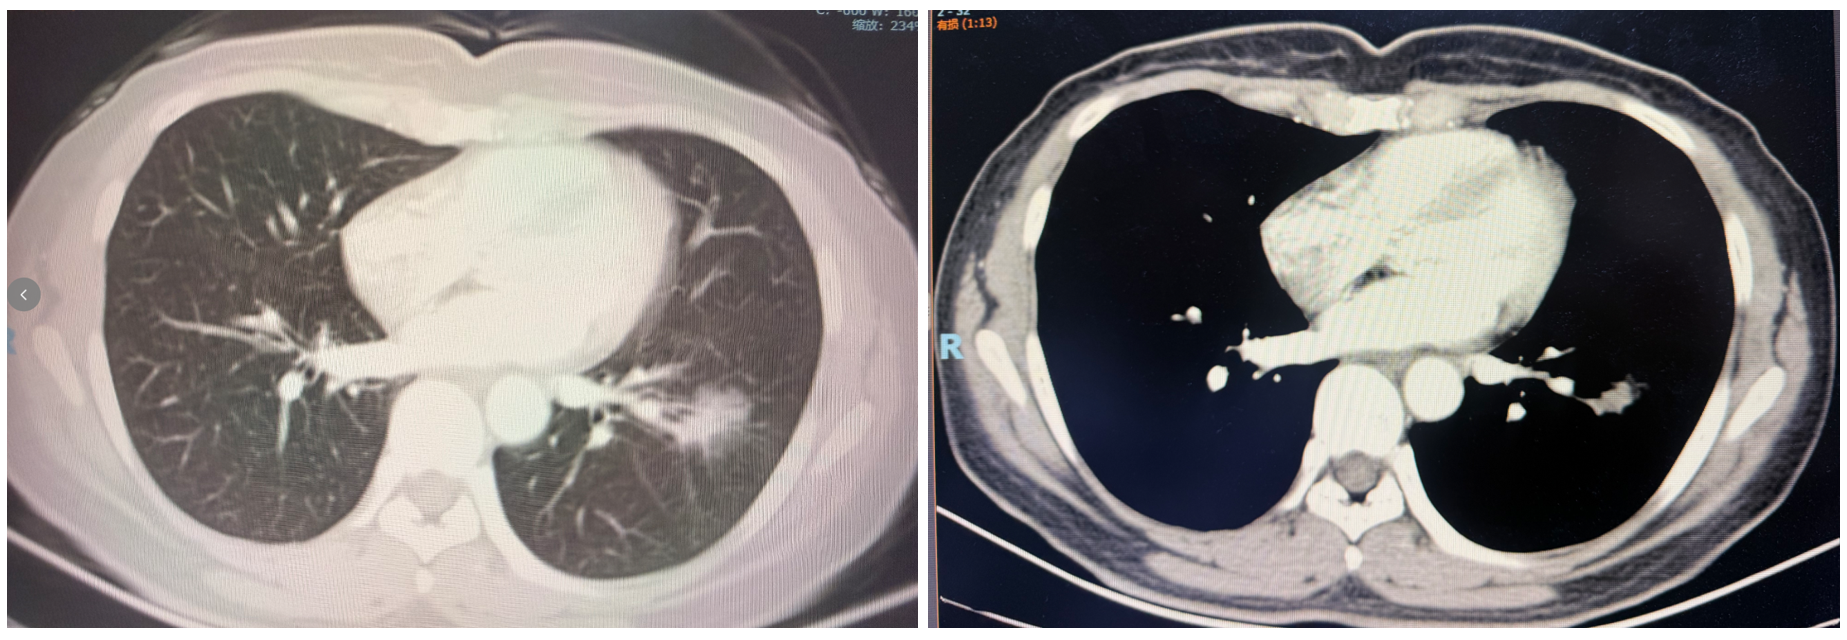

• 2026年1月22日复查胸部平扫CT:左肺术后部分缺如,断端可见吻合钉影;双侧纵隔未见增大淋巴结。患者术后恢复良好,疾病无复发迹象。

图4 2026年1月CT图像